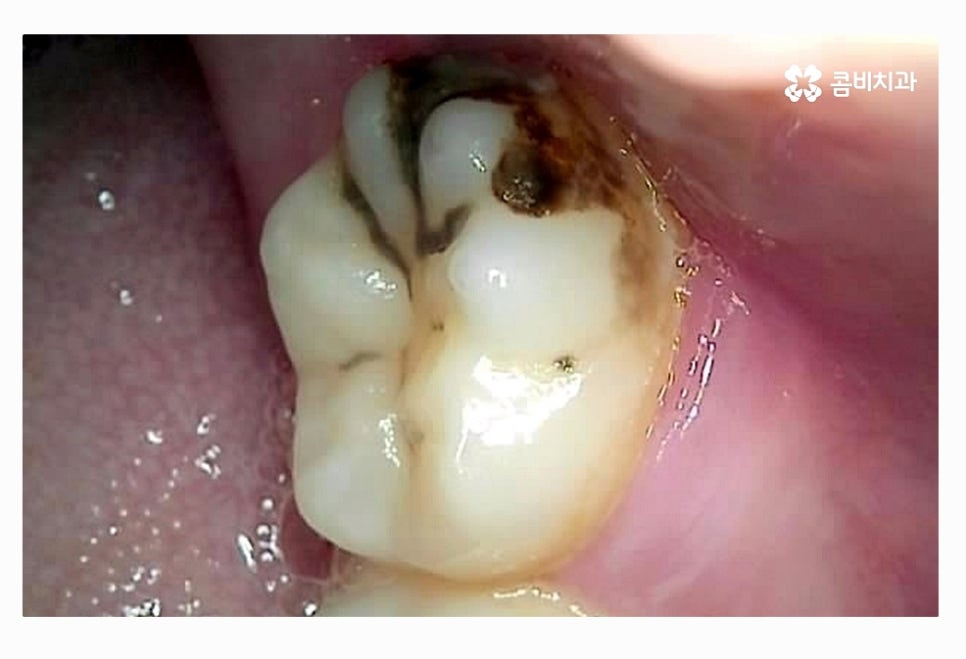

이미 사랑니 충치 심해진 상태라면 일반적인 충치 치료를

하는 경우보다는 대부분 발치를 한다고 볼 수 있어요.

물론 초기 충치의 경우 치료가 간단하기 때문에 치료를 하는 경우도

있지만 앞으로도 관리가 어려울 것으로 예상이 되거나

저작기능에 기여를 하지 않는다면 발치를 하는 것이

일반적인 상황이라 할 수 있어요.